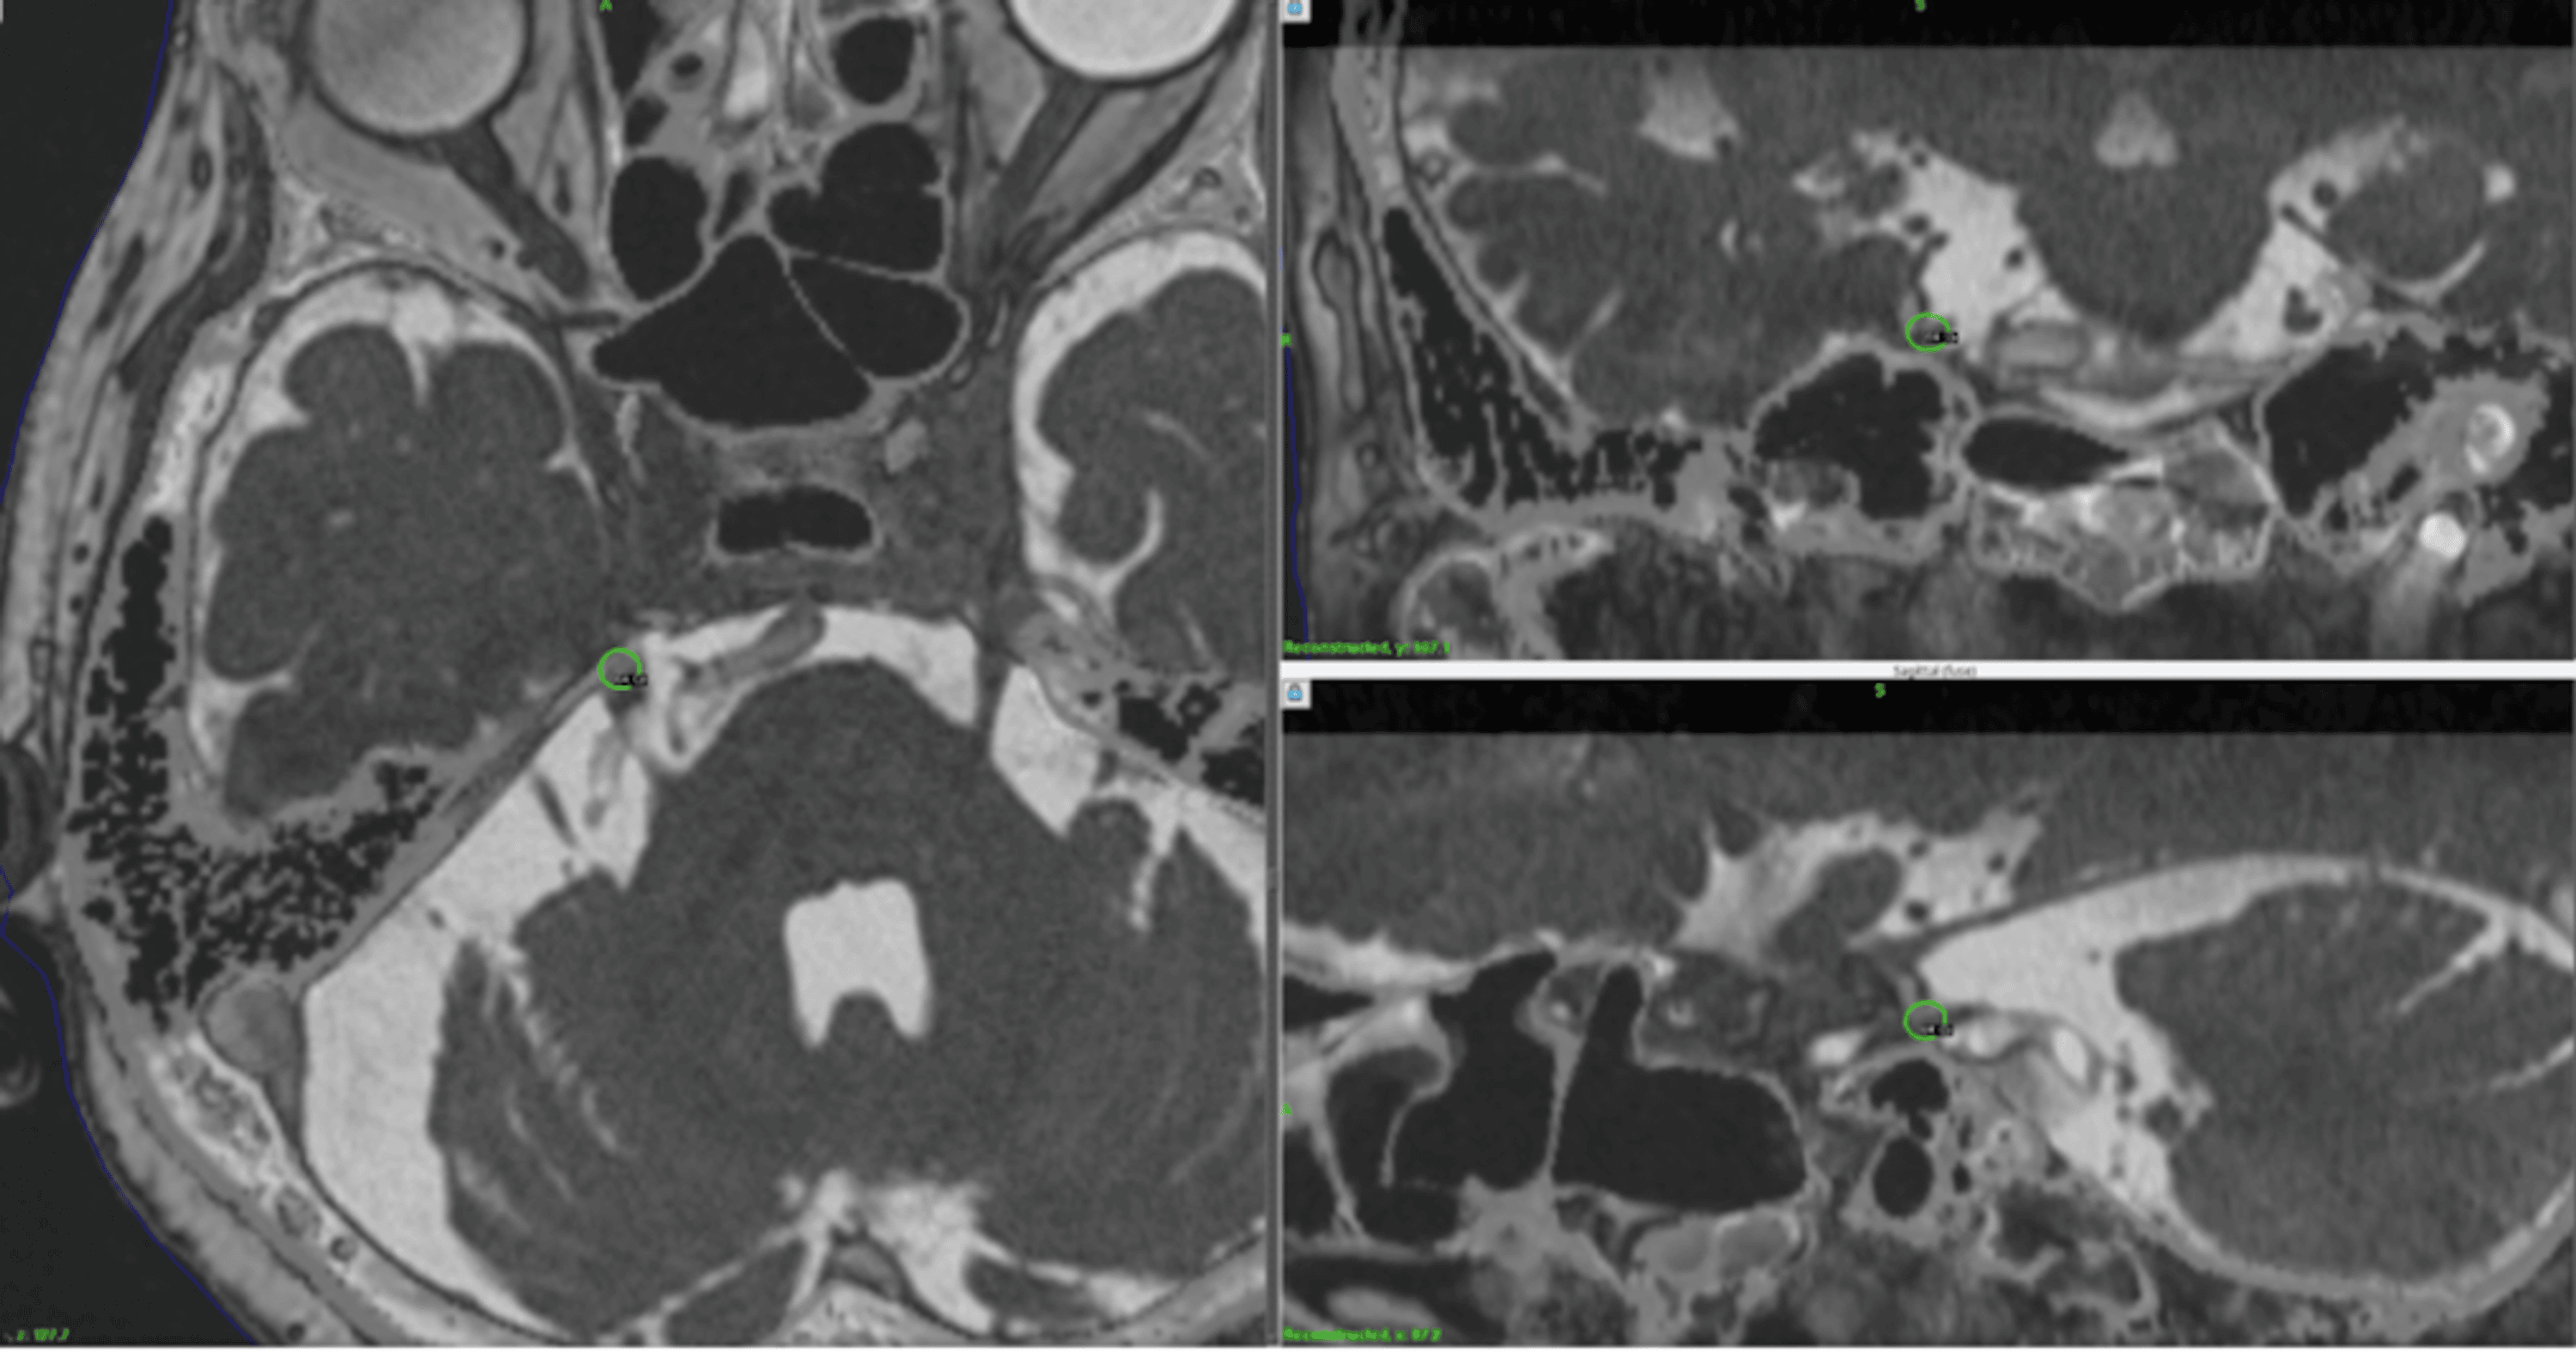

LINAC stereotactic radiosurgery for trigeminal neuralgia retrospective Stereotactic Radiosurgery For Trigeminal Neuralgia Trigeminal neuralgia is a chronic pain condition of the trigeminal nerve affecting 12 per 100,000 people. Stereotactic radiosurgery is an effective treatment option for trigeminal neuralgia (tn), with frameless stereotactic radiosurgery. Objectives the purposes of this study are to assess the effectiveness of cyberknife® stereotactic radiosurgery (srs) in. The aims of this systematic review are to provide an objective summary. Stereotactic Radiosurgery For Trigeminal Neuralgia.

Linacbased stereotactic radiosurgery for trigeminal neuralgia Stereotactic Radiosurgery For Trigeminal Neuralgia Trigeminal neuralgia is a chronic pain condition of the trigeminal nerve affecting 12 per 100,000 people. Radiosurgery was first attempted for trigeminal neuralgia in the early 1970s by lars leksell, who used the stereotactic technology. Stereotactic radiosurgery for trigeminal neuralgia: Objectives the purposes of this study are to assess the effectiveness of cyberknife® stereotactic radiosurgery (srs) in. Trigeminal neuralgia is. Stereotactic Radiosurgery For Trigeminal Neuralgia.